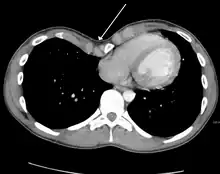

Physiologically, increased pressure in utero, rickets and increased traction on the sternum due to abnormalities of the diaphragm have been postulated as specific mechanisms.[9] Because the heart is located behind the sternum, and because individuals with pectus excavatum have been shown to have visible deformities of the heart seen both on radiological imaging and after autopsies, it has been hypothesized that there is impairment of the function of the cardiovascular system in individuals with pectus excavatum. While some studies have demonstrated decreased cardiovascular function, no consensus has been reached based on newer physiological tests such as echocardiography of the presence or degree of impairment in cardiovascular function. However, a 2016 meta-analysis found significant evidence that surgical correction of pectus excavatum improves patient cardiac performance.[14]

Pectus excavatum is initially suspected from visual examination of the anterior chest. Auscultation of the chest can reveal displaced heart beat and valve prolapse. There can be a heart murmur occurring during systole caused by proximity between the sternum and the pulmonary artery.[15] Lung sounds are usually clear yet diminished due to decreased base lung capacity.[16]

Many scales have been developed to determine the degree of deformity in the chest wall. Most of these are variants on the distance between the sternum and the spine. One such index is the Backer ratio which grades severity of deformity based on the ratio between the diameter of the vertebral body nearest to xiphosternal junction and the distance between the xiphosternal junction and the nearest vertebral body.[17] More recently the Haller index has been used based on CT scan measurements. An index over 3.25 is often defined as severe.[18] The Haller index is the ratio between the horizontal distance of the inside of the ribcage and the shortest distance between the vertebrae and sternum.[19]

Chest x-rays are also useful in the diagnosis. The chest x-ray in pectus excavatum can show an opacity in the right lung area that can be mistaken for an infiltrate (such as that seen with pneumonia).[20] Some studies also suggest that the Haller index can be calculated based on chest x-ray as opposed to CT scanning in individuals who have no limitation in their function.[21]